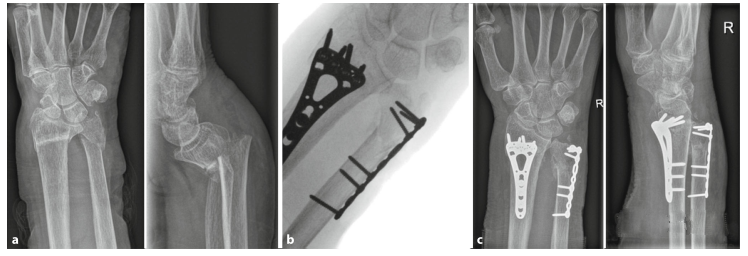

(6)Изображения до операции, во время операции и после операции пациентов с переломом дистального отдела лучевой кости в сочетании с переломом локтевой кости.